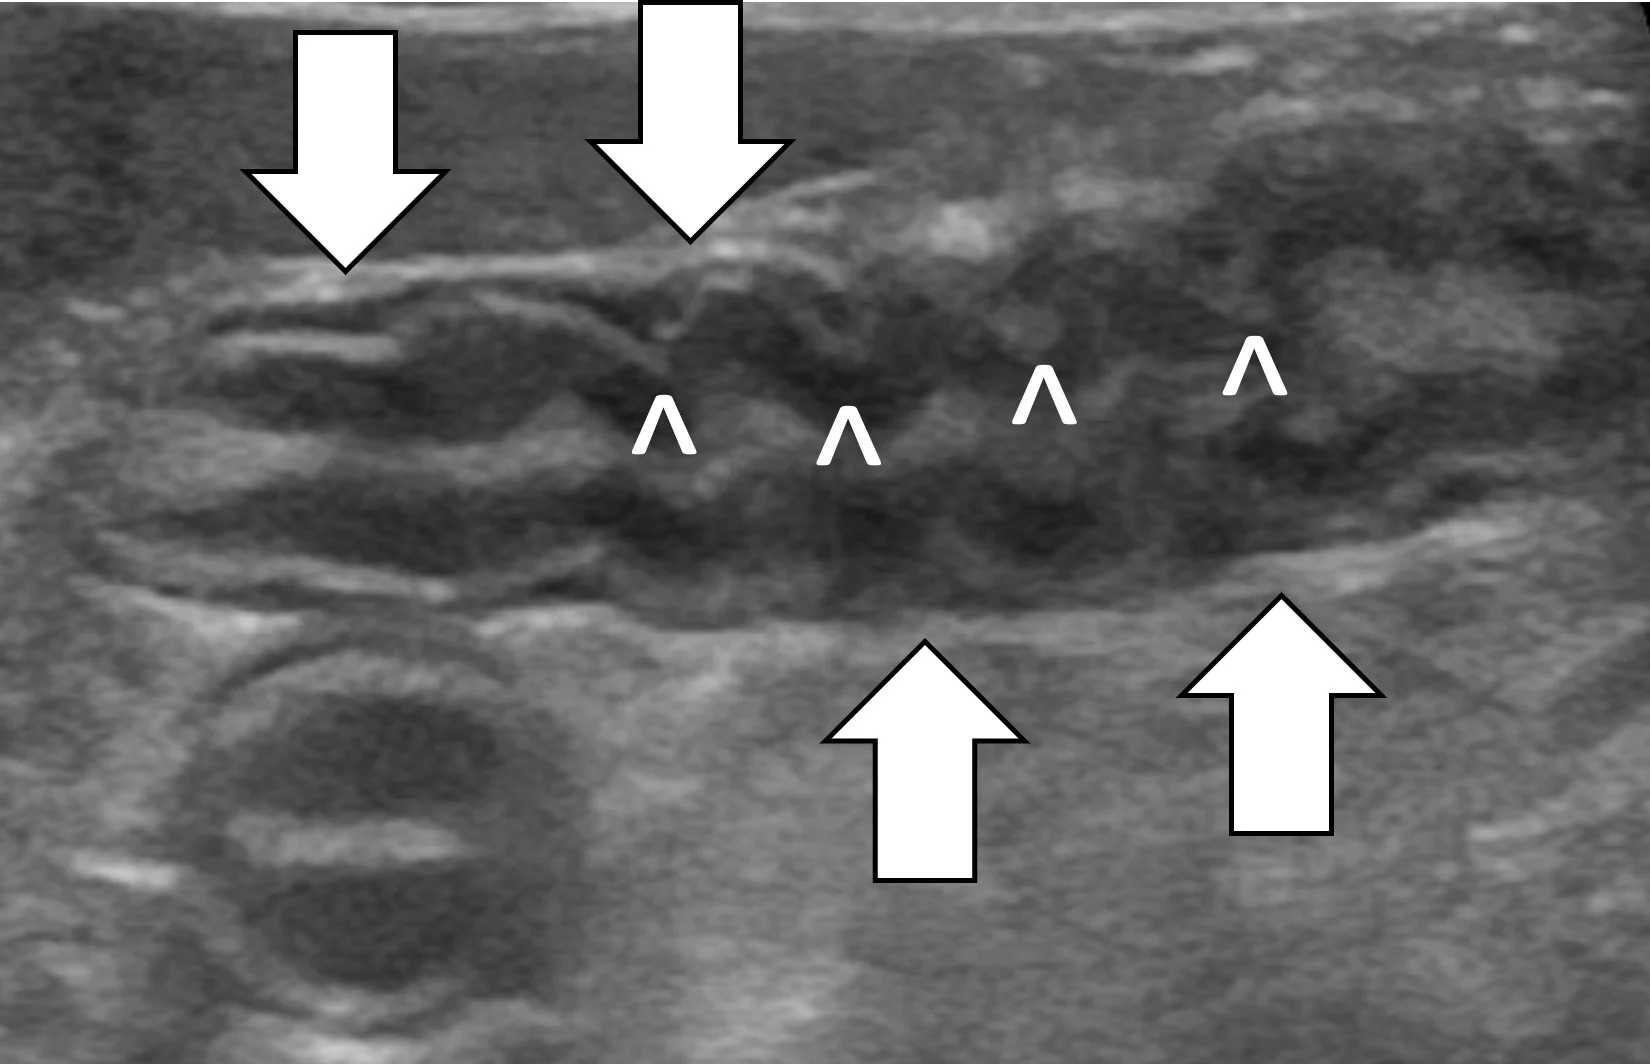

Linear foreign body obstructions occur when an object (eg, string, cloth) becomes stuck orally but extends aborally through the intestinal tract. Peristaltic contractions typically cause the small intestine to travel orally, eventually bunching. As a result, ultrasonographic findings include intestinal bunching (ie, plication) with or without a hyperechoic linear structure coursing through the lumen of the affected bowel (Figure 4).9-12 In some cases, trapped gas can cause a line that can be mistaken for the linear foreign body. Plication should not be confused with normal peristalsis or corrugation (Figure 5). With corrugation, the serosal margin is normal, and the mucosa and submucosa are undulant; with plication, the serosal margin is affected.14 In chronic cases, the mesentery surrounding the affected bowel may become hyperechoic, which can help identify the site of obstruction. Sterile inflammation and transudation may then result in focal accumulation of a small volume of free fluid. Mesenteric changes and peritoneal effusion also increase concern for bowel rupture and septic peritonitis. Patients may have concurrent findings of pyloric outflow or small intestinal mechanical obstruction, depending on the size and nature of the ingested cloth or string.

Abdominal ultrasound of an 8-year-old spayed miniature pincher with inflammatory bowel disease and pancreatitis. The mucosal and submucosal layers of a loop of jejunum are undulating (carets), but the serosal margin remains smooth (arrows).